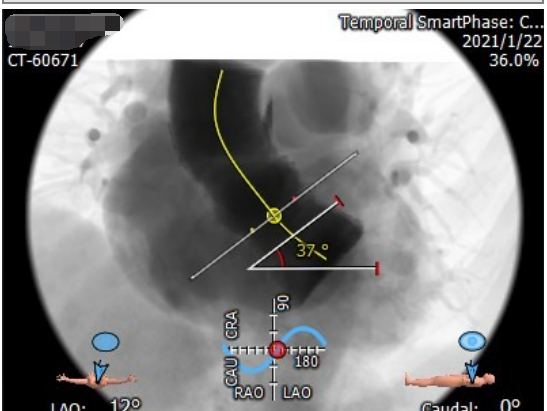

成功应用爱德华SAPIEN 3瓣膜

实施经导管主动脉瓣置换术(TAVR)

3月2日,在潘湘斌教授的带领下,我院结构性心脏病团队、心外科、心内科、麻醉科、体外循环科、复合手术室团队、超声科、重症医学科等多个科室通力完成了王婆的TAVR手术。

手术圆满成功,无明显瓣周漏,冠脉血液通畅。目前,王婆恢复状态良好,携家属送来了锦旗以感谢全体医护工作者,并拟于近日出院。